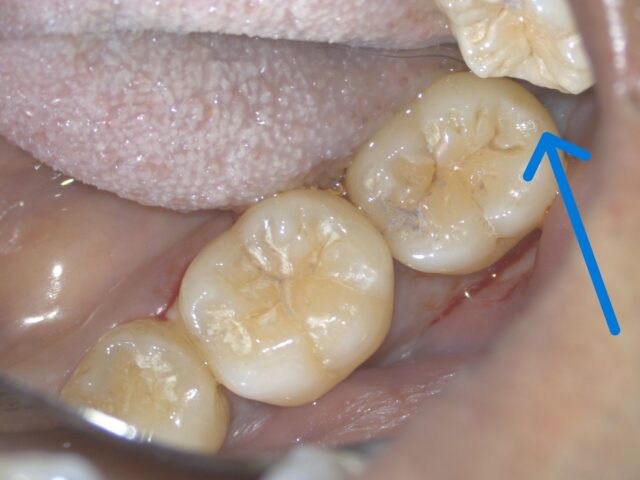

実際の口の中

口の中を上から見ても全く分かりません。

鏡を使って歯の裏側を覗き込むと、ようやく虫歯が確認できました。

治療後は、噛む方向から見ても全く分からないほど自然に仕上がりました。

7年後の口腔内写真とレントゲンです。

治療した部分は変わらず綺麗なまま。

再度虫歯になることもなく、非常に良い状態を保っています。